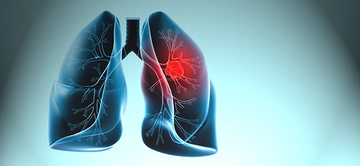

Akciğer tansiyonu, pulmoner hipertansiyon olarak da bilinen bu durum, akciğerlerdeki kan damarlarının basıncının normalden daha yüksek olması anlamına gelir. Bu rahatsızlık, kalp ve akciğer fonksiyonlarını etkileyebilir ve ciddi sağlık sorunlarına yol açabilir. Bu makalede, akciğer tansiyonunun insan sağlığı üzerindeki etkileri, belirtileri, nedenleri ve tedavi yöntemleri detaylı bir şekilde ele alınacaktır. Akciğer Tansiyonu Nedir?Akciğer tansiyonu, akciğerlerdeki kan damarlarındaki basıncın yükselmesi sonucu ortaya çıkar. Normalde, akciğerlerdeki kan damarlarının basıncı 8-20 mmHg arasında olmalıdır. Ancak bu değerlerin üzerinde bir ölçüm, pulmoner hipertansiyon olarak kabul edilir. Akciğer tansiyonu genellikle, kalp sağlığı üzerinde de olumsuz etkiler yaratır. Akciğer Tansiyonunun BelirtileriAkciğer tansiyonu, birçok belirti ile kendini gösterebilir. Bu belirtiler, hastalığın şiddetine göre değişiklik gösterebilir. Yaygın belirtiler şunlardır:

Akciğer tansiyonu, pulmoner hipertansiyon olarak bilinir ve akciğerlerdeki kan damarlarının basıncının yükselmesi durumudur. Bu durum, kalp sağlığını doğrudan etkileyebilir çünkü kalbin sağ ventrikülü, akciğerlerden gelen kanı pompalamak için daha fazla çalışmak zorunda kalır. Uzun vadede bu durum kalp yetmezliğine yol açabilir.